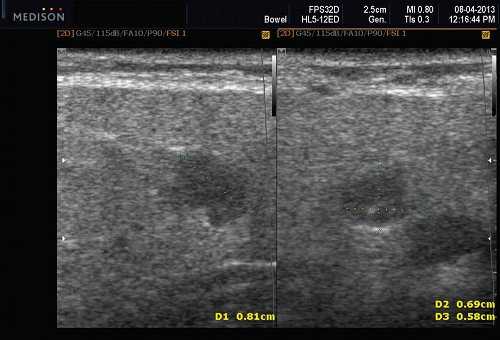

Теория и практический опыт в ультразвуковой диагностике патологии слюнных желез

В отечественной и зарубежной литературе встречается много работ, посвященных сиалогии (от греч. Sialon - слюна и logos - учение) - науке о заболеваниях и повреждениях слюнных желез, методах их диагностики и лечения. По данным разных авторов, на долю заболеваний слюнных желез приходится до 24% всей стоматологической патологии. В настоящее время в клинической практике наиболее часто встречаются дистрофические, воспалительные заболевания слюнных желез (сиалоаденозы, сиалоадениты), а также опухоли и врожденные пороки развития слюнных желез. Кроме того, патологические изменения слюнных желез часто сопутствуют другим заболеваниям (сахарный диабет, бронхоэктатическая болезнь, саркоидоз, цирроз печени, гипертриглицеридемия, лимфогранулематоз и др.).

- ультразвуковой метод (является наиболее доступным, безопасным и информативным в процессе дифференциальной диагностики патологического состояния слюнных желез).

Патология слюнных желез

Пороки развития СЖ встречаются редко. Наиболее распространены аномалии размера желез (агенезия и аплазия, врожденная гиперплазия (рис. 2) и гипоплазия), их расположения (гетеротопия, добавочные СЖ), аномалии выводных протоков (атрезия, стеноз, эктазия, кистозная трансформация, дистопии протоков).

Сиаладениты - большая группа полиэтиологических воспалительных заболеваний СЖ (рис. 3). Первичные сиаладениты - сиаладениты, рассматриваемые в качестве самостоятельных заболеваний (например, эпидемический паротит). Вторичные сиаладениты - сиаладениты, являющиеся осложнениями или проявлениями других заболеваний (например, сиаладенит при гриппе). Эхографическая картина при разной этиологии малоспецифична. Этиология имеет клиническое значение в процессе определения тактики лечения.

Рис. 3. Сиаладенит правой поднижнечелюстной слюнной железы.